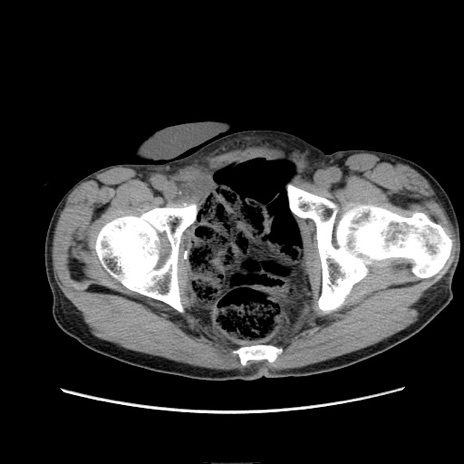

症例11(横断像)

【症例】 60歳代男性

【主訴】 下腹部痛

【現病歴】 本日夜中より下腹部痛の症状認め、受診。

【既往歴】 膀胱癌(膀胱全摘+尿管皮膚瘻術) 、胃癌術後

【身体所見】 BT 35.3℃、PR 58/min、BP 136/98mHg、腹部平坦、軟、腸蠕動音±、ストマ留置あり、左上腹部~正中部に圧痛あり、反跳痛なし。

【データ】WBC 5100、CRP0.01